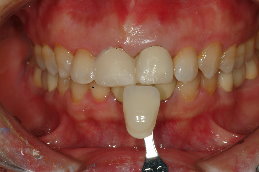

一、正面觀時(圖一),金屬邊緣明顯可見,陶瓷龜裂,陶瓷厚度明顯不足。

由於前牙的美觀相當重要,本院採用Cynovad數位比色機比色(圖四),並以高階數位單眼相機記錄牙齒的表面紋路及局部色澤(染色、斑點等)(圖五),因此技師即使未親臨現埸,仍可得到最精準的比色資料。